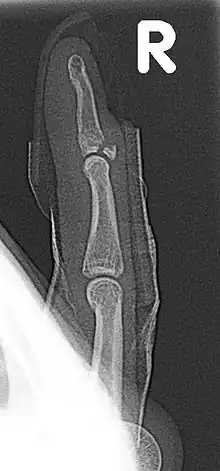

| Fracture of the dorsal base of the distal falange by extensor tendon avulsion (Busch fracture) | |

In medicine a Busch fracture[1] is a type of fracture of the base of the distal phalanx of the fingers, produced by the removal of the bone insertion (avulsion) of the extensor tendon. Without the appropriate treatment, the finger becomes a hammer finger. It would correspond to the group B of the Albertoni classification.[2] It is very common in motorcycle riders and soccer joggers, caused by hyperflexion when the tendon is exercising its maximum tension (the closed hand tightening the clutch lever or the brake lever).[3][4]